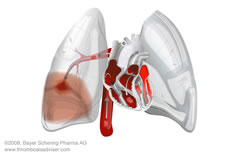

Tromboembolia Pulmonar: Se caracteriza por la formación de un coágulo que ocluye el riego sanguíneo de los pulmones que proviene de alguna parte del cuerpo, mas comúnmente de los miembros inferiores. Esto en los casos más severos puede ocasional fracaso del corazón derecho. Los síntomas son aparición súbita de dificultad respiratoria, baja de oxigeno en la sangre, taquicardia y ocasionalmente dolor en el tórax.